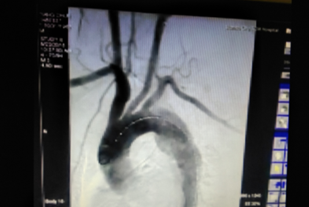

術(shù)后(見主動脈血流規(guī)則,治療效果良好)

“微創(chuàng)腔內(nèi)治療技術(shù)給患者帶來了福音?!蔽河钫f。手術(shù)僅需行腹股溝部的小切口,在X線監(jiān)視屏監(jiān)測下通過微創(chuàng)介入的方法將覆蓋人工血管的金屬支架精確植入到有問題的血管,從而將血流與問題管壁隔絕。手術(shù)難度很大,風(fēng)險極高,醫(yī)生操作需要非常謹(jǐn)慎,支架需精確植入到病變位置。手術(shù)能實現(xiàn)與開腹手術(shù)相同的治療效果,但避免了開腹手術(shù)引起的創(chuàng)傷及相關(guān)并發(fā)癥,術(shù)后恢復(fù)時間也遠(yuǎn)遠(yuǎn)短于外科手術(shù),一般2-3天即可。